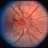

- Lyme disease, intraretinal hemorrhage, periopticneuritis

- Papilledema, intra-retinal hemorrhage, periopticneuritis.